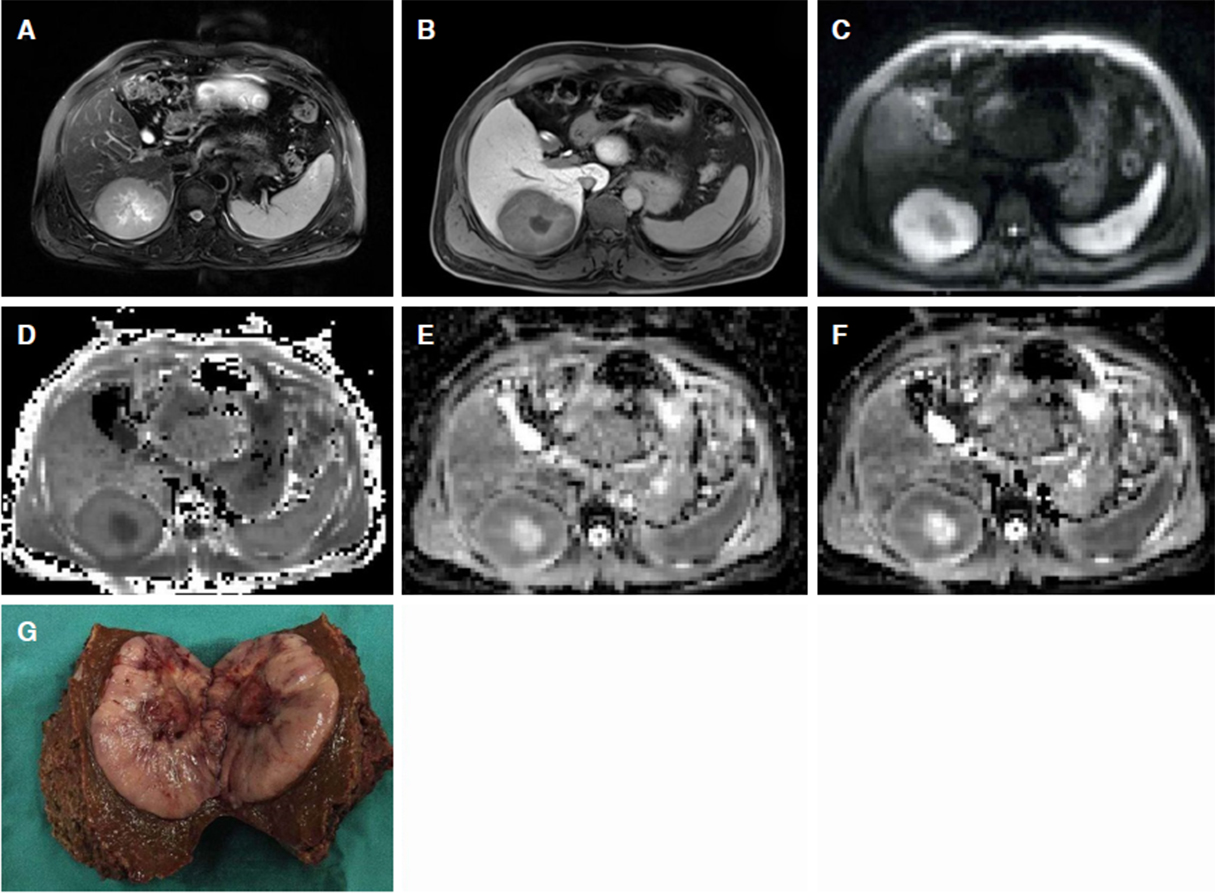

Diffusion kurtosis imaging (DKI) is an attempt to provide a more accurate model of diffusion, and to reflect tissue heterogeneity in non-Gaussian diffusion behavior[36]. Recently, our team validated the performance of DKI in predicting the degree of differentiation of HCC[37]. The results showed that mean apparent kurtosis coefficient (MK) and ADC values are significantly correlated with the grade of HCC [Figure 1]. In addition, the MK value represents a higher specificity than the ADC in differentiating high-grade from low-grade HCCs. We speculated that this might be due to the fact that increased tumor cellularity results in decreased extracellular space and the restricted diffusion of water molecules, which is visually presented as decreased ADC and MD in higher-grade HCC. Furthermore, a higher MK value may be an independent risk factor for early tumor recurrence and poor prognosis in HCC patients, which might be related to the higher-grade of HCC that often tend to be more proliferative, aggressive and heterogeneous, and result in a more irregular tumor microstructure[38].

Figure 1. A 48-year-old male with a pathologically confirmed HCC with MVI. A 7.8 cm × 6.0 cm tumor in the right posterior hepatic section shows slight hyperintensity on T2-weighted image (A), hypo-intensity relative to the surrounding liver parenchyma in hepatobiliary phase (B), and restricted diffusion on the DWI with a b-value of 700 s/mm2 (C). MK map (D) shows higher signal intensity of tumor compared with that of background liver parenchyma. ADC (E) and MD (F) maps show lower signal intensity compared with that of liver parenchyma. The calculated mean values of MK, ADC, and MK for the tumor were 0.99, 1.10 × 10-3 mm2/s, and 1.28 mm2/s, respectively. The pathological results after tumor resection demonstrated HCC [Edmondson-Steiner (III) with positive MVI (G)]. HCC: hepatocellular carcinoma; DWI: diffusion-weighted imaging; ADC: apparent diffusion coefficient; MD: mean diffusion; MK: mean apparent kurtosis coefficient

Multiple morphological imaging biomarkers including non-smooth tumor margins, irregular rim-like arterial phase hyperenhancement, tumor multifocality, and “mosaic” architecture, are reported to be highly correlated with MVI in HCC[62-64]. DWI and its-derived technologies have also shown great potential in detecting MVI in HCC. The mean and minimum ADC values of HCCs with MVI are reported to be lower than those of HCCs without MVI[65]. In addition, a higher MK value on DKI and irregular rim enhancement pattern are highly correlated with the presence of MVI[66]. Similar results were reported in our previous study[37][Figure 1]. The mechanism underlying these results may be associated with the formation of a more complex microenvironment induced by MVI, such as the presence of tumor cell proliferation, necrosis, or inflammatory damage[67].Therefor, a greater packed cell structure and more irregular, heterogeneous environments are likely to occur in HCC with MVI, resulting in increased tissue diffusion, which manifest as increased MK[66,68]. Furthermore, hypo-intensity on HBP images on Gd-EOB-DTPA enhanced-MRI in conjunction with other clinical indicators has been proven to further improve the prediction of MVI in HCC, and is superior in predicting early recurrence and the survival rate in HCC patients[69,70].